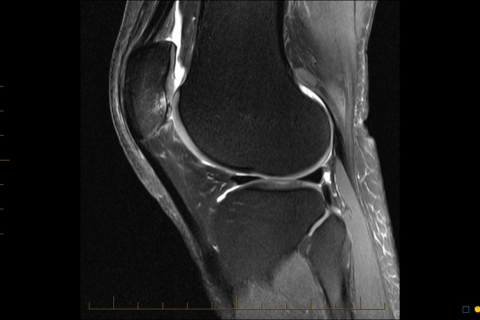

Our program prepares radiologists for the high-level provision of musculoskeletal (MSK) imaging services. The goals are to provide advanced training in MSK radiography, CT, MRI, and image-guided intervention. Fellows will receive 1:1 teaching with sub-specialist radiologists, engage in self-directed study based on a formal curriculum, and participate in multidisciplinary conferences, orthopaedic and sports medicine meetings, and journal clubs.

The program offers balanced exposure to both hospital and community-based MSK imaging, with opportunities to develop expertise in sports medicine and orthopaedic imaging. Alongside clinical duties, fellows will participate in educational activities and research projects to prepare for integrating advanced MSK imaging skills into general or specialist private radiology practice. At the completion of the program, a fellow can expect to be proficient in the supervision and interpretation of MSK imaging studies acquired from a range of CT and MRI platforms.